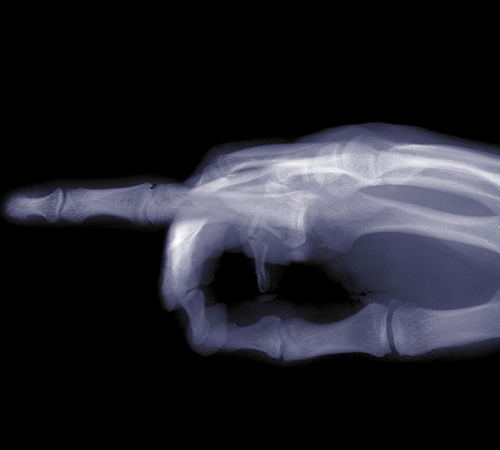

방아쇠수지

• 정상

• 방아쇠수지

손가락을 구부리고 펴는 것을 관장하는 굴곡건에 염증이 생긴 질환입니다.

손가락을 움직일 때 ‘딱’ 하는 마찰음이 난다고 하여 방아쇠 수지라고도 불립니다.

• 방아쇠수지 진단

손가락에 나타나는 통증 부위와 손가락을 쥐고 펼 때의 느낌 등

그 증상이 뚜렷하게 나타날 경우, 의료진의 의학적 검사만으로도 진단이 가능합니다.